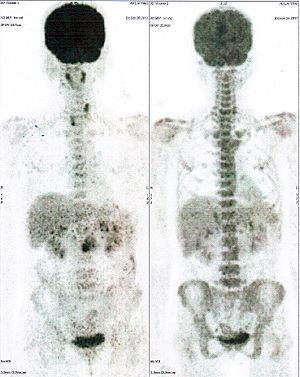

CASE NO: 1 - A FEW MONTHS LATER

A few months after successful treatment for hepatocellular carcinoma, and partially successful for stomach cancer, the PET/CT scan showed the stomach cancer becoming very active, with several metastases to the parts of the liver not previously involved by hepatocellular carcinoma. After a few treatment, all the active stomach cancer lesions in the stomach and in the liver went into remission.